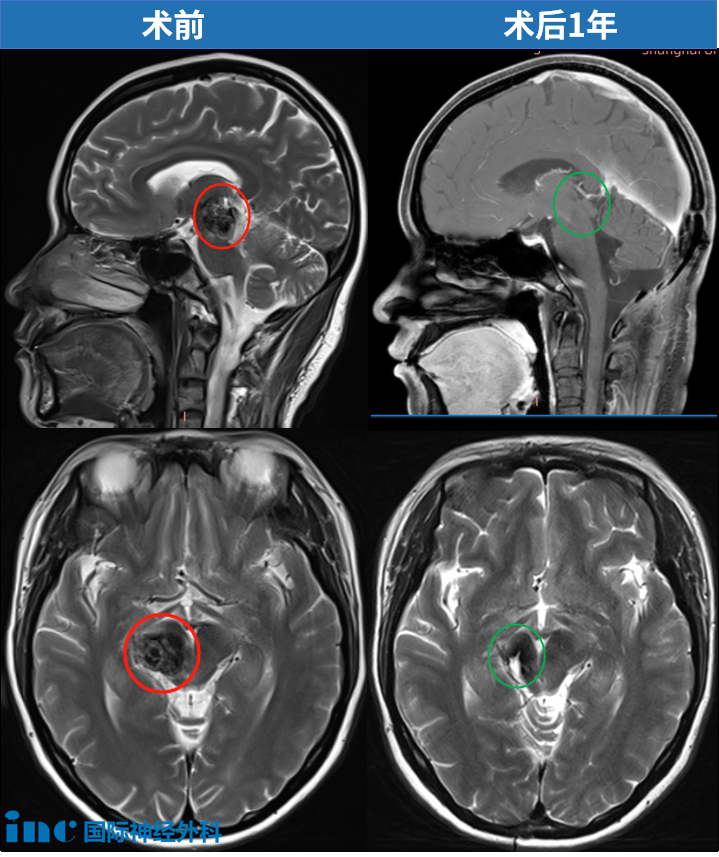

37歲女性丘腦海綿狀血管瘤

37歲的思睿,在大家眼中一直是“溫暖的小太陽”。2018年,丘腦出血導(dǎo)致思睿復(fù)視、記憶障礙、左半身偏癱,連簡單的抓握都成了奢望。醫(yī)生坦言:“手術(shù)風(fēng)險太大,后遺癥可能比現(xiàn)在更嚴(yán)重。”無奈選擇保守治療,直到第2次出血,只能臥床休息時,她感到后怕——“之前是我太輕視了!”最終巴教授為她順利全切丘腦-中腦海綿狀血管瘤,術(shù)后第1天四肢活動正常、術(shù)前癥狀緩解。

術(shù)后1年,最新核磁顯示海綿狀血管瘤已被完整切除!視頻中她的整體臨床狀態(tài)非常好。巴教授表示在經(jīng)歷過如此巨大中腦/丘腦海綿狀血管瘤手術(shù)后,能有如此良好的術(shù)后恢復(fù),實(shí)屬罕見!點(diǎn)擊閱讀:37歲媽媽歷時7年戰(zhàn)勝“手術(shù)禁區(qū)”腦干腫瘤,堅(jiān)持的力量強(qiáng)的沒邊了!